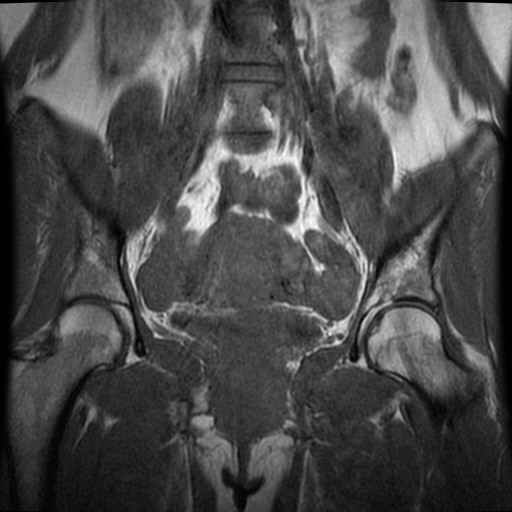

Bekken